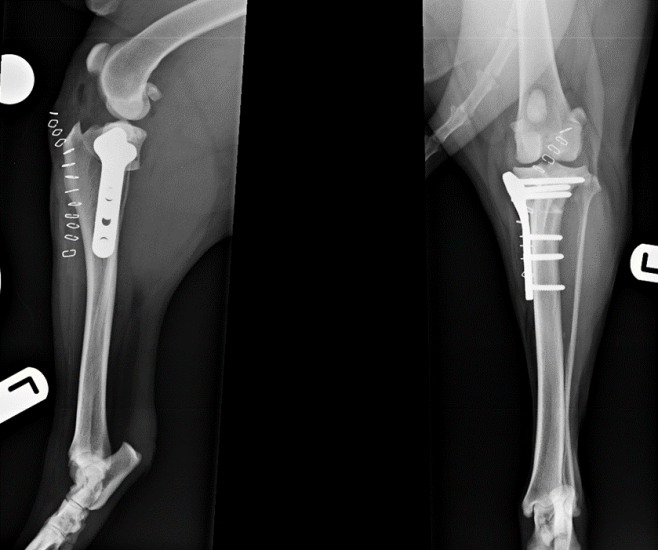

Figure 1. Tibial plateau levelling osteotomy using a broad locking plate and screws in a 45kg Labrador